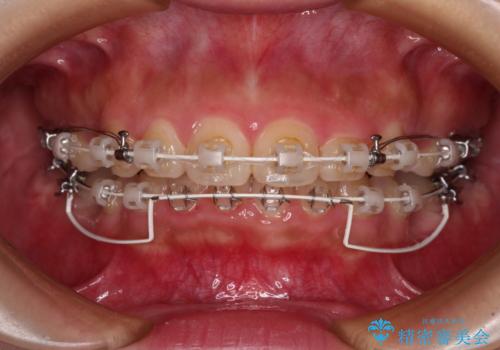

- 審美装置

骨格的な上顎前突であり、上下前歯の前後的な距離が大きいため、上顎は左右第一小臼歯を、下顎は左右第二小臼歯をそれぞれ2本抜歯することで前歯が接触するようにし、さらには奥歯の咬み合わせも、より理想的な状態へ近づけていくこととしました。

3年以上はかかる難症例であるため、表側のワイヤー装置にて治療を行うこととしました。